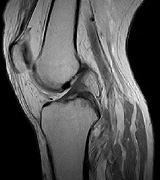

MRI画像

• mri01

• mri02

• mri03

• mri04